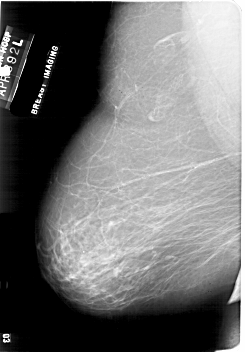

A_1862_1.RIGHT_MLO

RIGHT_MLO LINES 6871 PIXELS_PER_LINE 4336 BITS_PER_PIXEL 12 RESOLUTION 43.5 NON_OVERLAY